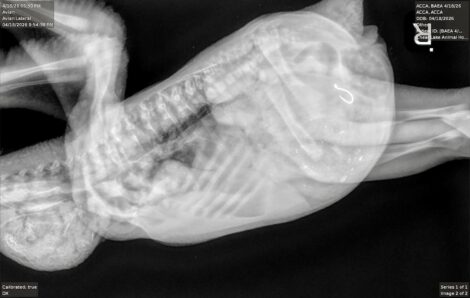

- The baby eagle’s X-ray shows the fishhook. (Photo courtesy Tricia Mayle, Avian Conservation Center of Appalachia)

The baby eagle's X-ray shows the fishhook. (Photo courtesy Tricia Mayle, Avian Conservation Center of Appalachia)